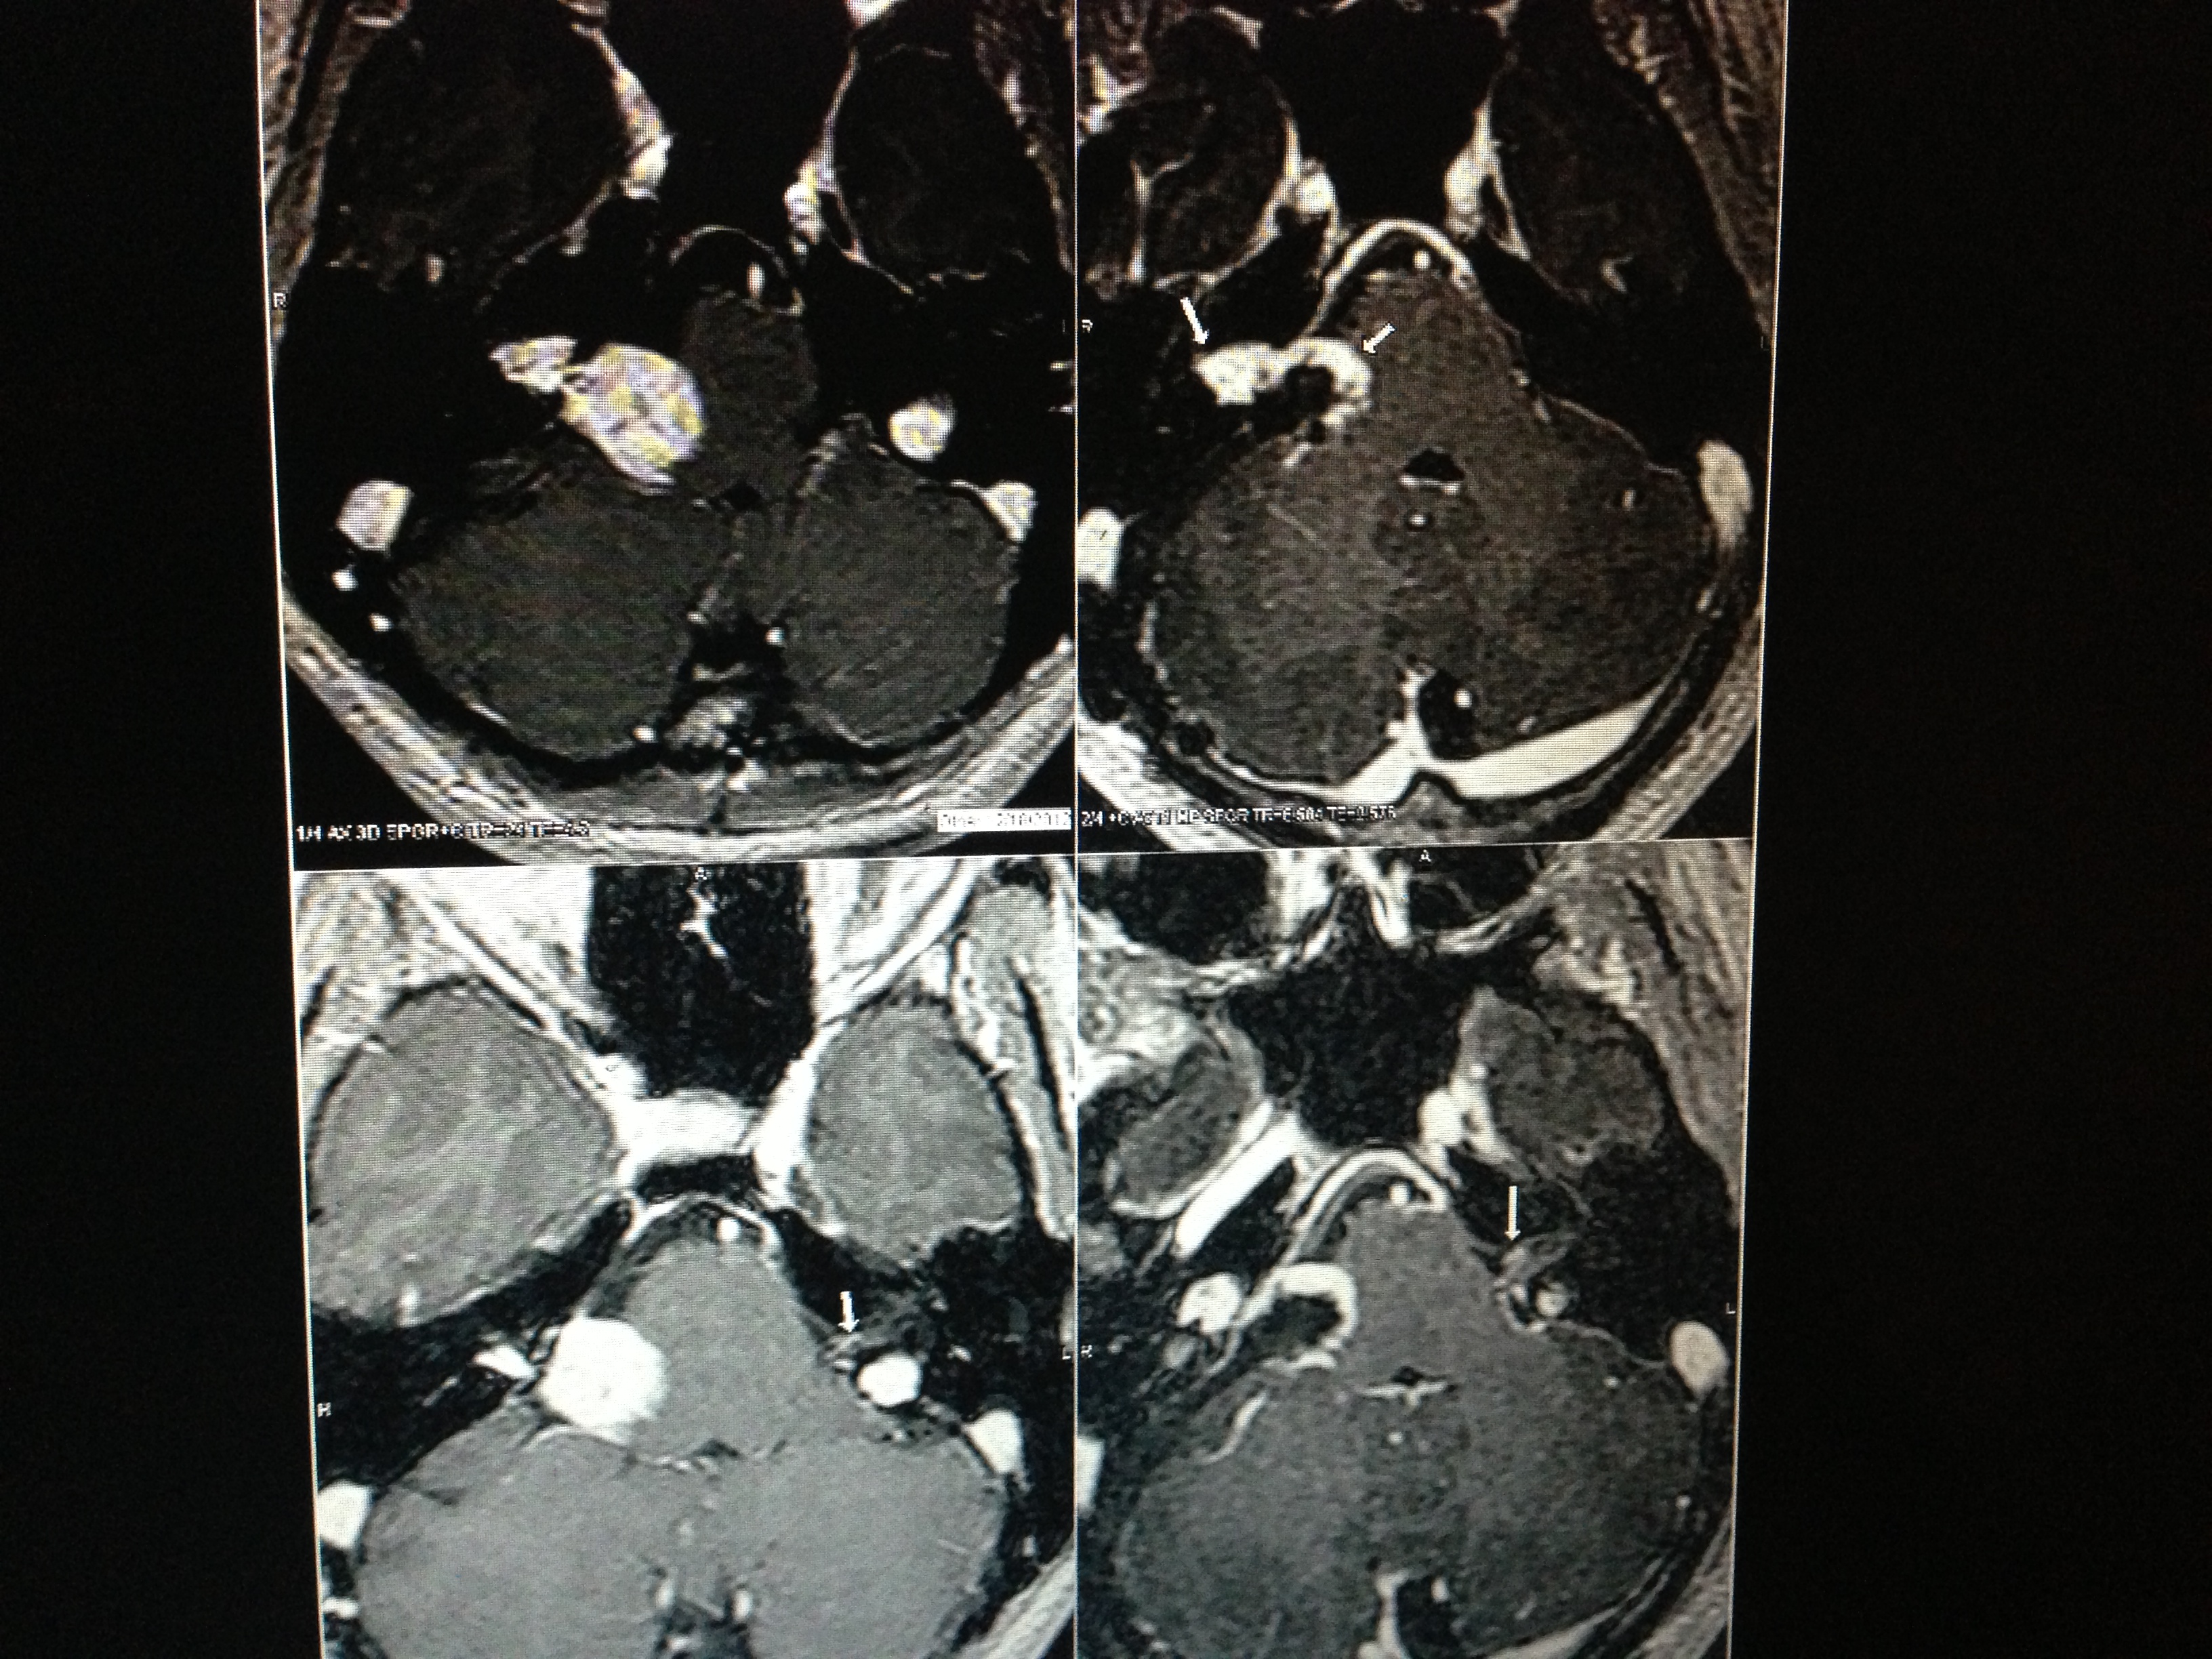

I had my birthday this month and it was different from last year. Last year I had a tearful lunch with a friend, tears of joy that I made it. I moved slowly from lunch, to the car, to home to bed. I needed to be in bed before birthday dinner. Too tired to change out of my birthday dress, I curled up in my childhood bedroom at my parents house in a beautiful dress, plunked my computer on my lap and thought I’d just take a break. What I quickly realized is that when you have no idea what recovery will be like and you just had your first brain surgery, you don’t really know what it means to take a break. I put my MRI in the computer, I combed through reports about irregularities and tried to envision new tumor sizes as compared with old tumor sizes. I would text my sister pictures and ask her to identify things. Little did I know I was looking at completely the wrong thing, it really didn’t matter what I was trying to look at, I was seeing a lot of things and they all looked like they could be a match to the overly clinical complicated words in the report, so I panicked. Using the tech available to me in bed, I grabbed my cell phone and took a picture of the MRI on the computer and sent it to my sister.

“WHAT IS THAT?” I said with force when she called me. I had sent her this picture:

She plainly could not tell what I was looking at and me saying, tht nodule next to the broccoli to the right of the other nodule was not helpful. So I searched through the phone for an app that could put an arrow on a picture. I couldn’t find one, so I improvised. I sent her this:

Hmm, fine. I learned later when I looked at the MRI with my doctor, they already put little arrows where you are supposed to look, so you don’t really need to scour your iPhone apps to find a space helmet that fits perfectly over what is worrisome. If you look back at the first pic, you’ll see the arrows if you bother to look hard enough. Whoops. I was so busy panicking over blood vessels I had obscured the things I was really supposed to be looking at. I couldn’t see what was plainly right in front of me. I couldn’t see any of it. It was my birthday, I was alive, and I was worrying about the potential of the thing that didn’t kill me yet that might cause me a problem that I could not fix or address from my bed anyway.